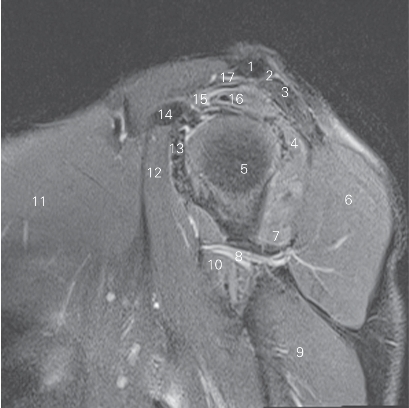

图4-21 经肩锁关节的矢状断层MR T2WI FS

1 锁骨 clavicle 2 肩锁关节 acromioclavicular joint

3 肩峰 acromion 4 冈下肌 infraspinatus

5 肱骨头 head of humerus 6 三角肌 deltoid

7 小圆肌 teres minor

8 腋神经及旋肱后动脉 axillary nerve and posterior humeral circumflex artery

9 肱三头肌 triceps brachii 10 大圆肌 teres major

11 胸大肌 pectoralis major 12 喙肱肌 coracobrachialis

13 肩胛下肌 subscapularis 14 喙突 coracoid process

15 肩袖间隙 rotator interval 16 冈上肌 supraspinatus

17 喙肩韧带 coracoacromial ligament